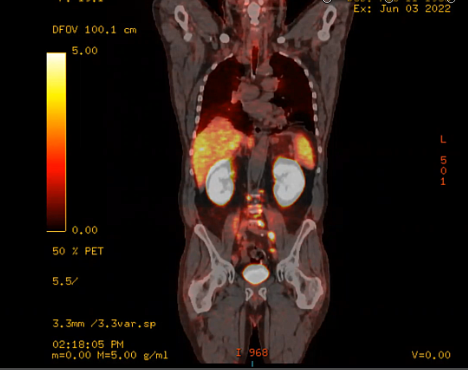

urethral tumor, urothelial carcinoma, PET, CT, palliative treatment, mediastinal nodes, biopsy, prostate gland, PSMA, false positive, pelvis with nodes, bone lesions, PSA, bladder